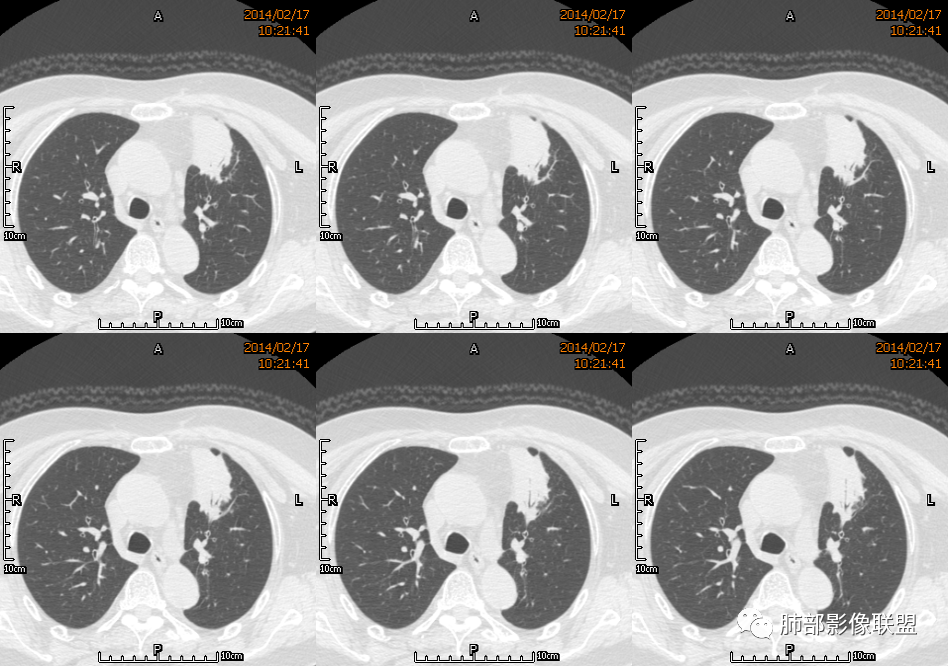

薏米: 老年女性,急性起病,咳嗽,咳痰,咯血,白细胞低,胸部CT提示左肺上叶可见一团块样密度增高影,边缘平直,部分略有膨隆,内可见支气管进入后截断,小的空洞,血管造影,坏死,明显强化,周边可见少许索条,考虑炎性病变,肺脓肿可能。鉴别结核,隐球菌。

一切∮随缘: 定位:肺内,左肺上叶肿块,呈长条状,平行血管束生长,边缘分叶,平扫密度均匀,增强后不均匀强化,可见低密度坏死,近段支气管及血管穿行病灶内,远端堵塞支气管,血管似有破坏,周围散在点状小结节,及纤维索条影,考虑恶性:腺癌,类癌,淋巴瘤。鉴别结核及隐球菌。

红星: 老年女性,咳嗽咳痰10天,痰中带血4天。左肺上叶前段胸膜下肿块影,沿支气管方向走行以膨胀生长为主,局部有收缩改变,支气管血管绝断,中间有小片状的坏死及小的空洞影,增强扫描病灶明显的强化,病灶周围网格状的小叶间隔增厚。拟左肺上叶前段浸润型腺癌并癌性淋巴管炎。鉴别诊断结核肉芽肿。

秦化君: 左肺上叶前段胸膜下软组织密度肿块影,边缘清晰,部分边缘膨隆,纵隔缘弧形内凹,脂肪界面清晰。肿块中心密度减低,支气管进入病灶后截断,似有扩张表现,病灶周围可见小叶间隔增厚,斑片影,近端支气管似管壁增厚。增强后明显强化,中心见低密度区。考虑:1.肉芽肿性炎?2.IMT?3.淋巴瘤?

傅昌瑜: 老年女性,咳嗽咳痰10天,痰中带血4天。左肺上叶前段胸膜下肿块影,沿支气管方向走行,膨胀生长为主,局部边缘似有收缩改变,中间有小片状的坏死,支气管进入,增强扫描病灶明显的强化,血管走形较自然(血管漂浮征?),病灶周围网格状的小叶间隔增厚。考虑淋巴瘤可能性大,注意鉴别炎性肉芽肿及肺腺癌。

水晶石头: 患者老年女性,咳嗽咳痰10天,痰中带血4天余。查血常规白细胞低;肿瘤标志物、凝血功能正常;血生化:蛋白低;C反应蛋白、血沉稍升高。胸部CT:左肺上叶前段胸膜下沿气管支气管走形肿块影,长轴与胸膜平行,见分叶、毛刺、支气管截断、空泡征象。增强明显强化,且见血管造影征及病灶内小灶低密度坏死区。左肺上叶尖后段见一结节灶。综合考虑恶性病变可能大,腺癌或淋巴瘤可能。鉴别诊断肺脓肿。

尘缘: 老年女性,咳嗽咳痰10天,痰中带血4天,白细胞及中性粒明显减低,轻度贫血。影像表现:左上叶肿块,边缘膨隆,局部平直,支气管稍扩张,进入后远端堵塞,内见小空洞及不规则坏死区,增强后强化明显,坏死边界较清,并见环状强化区,内部血管走行自然,周围见小叶间隔增厚呈大网格征。初步诊断:慢性炎性伴脓肿形成及肉芽组织增生。鉴别淋巴瘤及腺癌,先抗炎治疗后复查或直接穿刺明确。

张延军: 左肺上叶前段软组织影,偏下缘见充气支气管,部分支气管壁与肿块近端增厚狭窄。实性部分见血管穿行,边缘平直并局限性凹陷,增强扫描内见斑片状低密度区,界不清,实性部分中度强化,病变外宽内窄,基底贴于胸壁,周围肺组织内见条片状密度增高影,考虑炎性,结核?腺癌待排。

毛勤香: 老年女性,左肺上叶胸膜下肿块,部分膨隆部分收缩,边缘毛糙模糊,周围少许索片状影,小叶间隔增粗,支气管进入后截断,增强扫描明显不均匀强化,内低密度区无明显强化,血管走行尚可,首先考虑感染性变并脓肿形成,鉴别淋巴瘤,建议抗炎后复查。

宇宙星空: 外大内小,近端支气管壁增厚,爬树征,内部坏死不均匀,都比较典型了。支持结核,鉴别炎性肉芽肿、慢性脓肿。

王崇军: 老年女性,咳嗽咳痰10天,痰中带血4天。左肺上叶前段胸膜下 肿块影及段形态密度增高影,沿支气管方向走行,膨胀生长为主,局部有收缩改变,支气管进入并闭塞,中间有小片状的坏死及小的空洞影,空洞漂浮在坏死边缘,增强扫描病灶明显的强化,坏死边界清楚,似乎有轻度强化环,病灶周围网格状的小叶间隔增厚及小结节影,外侧胸膜呈糊墙改变。考虑为肺脓肿,这么大的病灶,竟然没有发烧,白细胞低,CPR轻度升高,均与脓肿不符,所以恶性待排,短期抗炎治疗后复查,病灶没有变化,脓肿就可以排除,恶性基本可以确定。

空格: 临床特点:老年女,血糖略高,低蛋白血症,白细胞低,提示有免疫下降的存在。机会性感染存在机会。黄浓痰一般常见于炎性病变,痰中带血则肿瘤多见,两厢pk,觉得黄脓痰胜,除非肿瘤继发感染一般不会黄脓痰。影像:一 、良性征像:1.病灶整体是个尖端指向肺门的三角形病灶;2.胸膜平直,胸膜外少量液体糊墙;3.支气管未见明显截断,内壁毛糙?4.近端支气管弥漫性增厚,结核脓痰咯出,看做引流支气管;5.多个层面病灶呈直边征,多角征,无明显分叶;6.病灶内坏死边缘光整,伴小气泡。小叶间隔增厚光滑锐利,无结节,不太像癌淋。二、恶性征像:部分层面向胸膜外突,略有占位效应。总体考虑感染性病灶,霉菌可能。结核抗体阴性,可以排除?

刘和林: 老年女性,咳嗽咳痰10天,痰中带血4天。左肺上叶前段胸膜下 肿块影,沿支气管方向走行,膨胀生长为主,局部边缘似有收缩改变,中间有小片状的坏死,坏死区内见小气泡,支气管进入、部分填充、部分末端稍显扩张,增强扫描病灶明显的强化,周围肺不干净,其上肺见小叶间隔增厚。肺癌、淋巴瘤、炎性肉芽肿?肺癌:支气管末端稍扩张,周围类似树芽征改变,不太符合。淋巴瘤:数个小气泡,明显强化,周围树芽征样改变,不太符合。

2.左肺上叶前段胸膜下块状影,不规则呈“逗点样”延向肺门区,边界清楚,未见分叶、毛刺及张力,表面不规则棘突,状如“火焰”或“日冕”。相邻胸膜增厚,未见栽赃、卫星病灶。

3.病灶密度不均,中央坏死液化并见气泡影,支气管及血管贴边进入,较均匀环形强化(显示多层结构),未见明确壁结节。